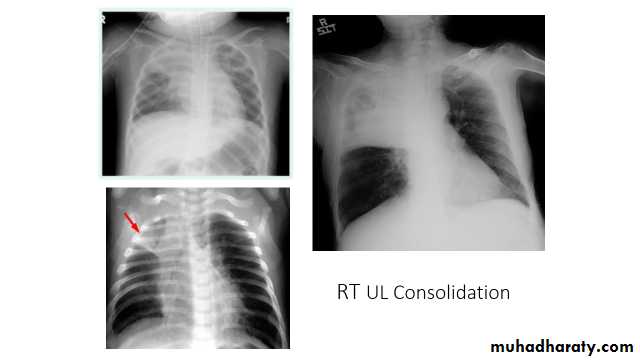

Right upper lobe consolidation

RUL consolidation will be seen as an increased opacity within the right upper lobe. Opacity may be sharply bordered by the horizontal fissureSome loss of outline of the upper right heart border may be apparent

Radiological sign in chest radiograph

Dense opacity seen above the horizontal fissure.

Air-bronchogram line

The lower border of the consolidation is sharply delinated by the horizontal fissure suggesting it lies in the anterior segment of the RUL